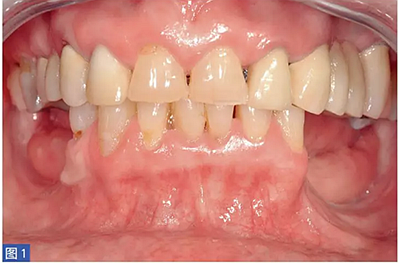

在整個手術(shù)過程中以及術(shù)后12 個月都要評估并發(fā)癥的發(fā)生。在術(shù)后12 個月,患者都要通過視覺模擬量表(VAS)對手術(shù)的滿意度從0(非常不滿意)到10(非常滿意)進行評估。這些問題針對對于治療過程的主觀評價。圖1-12 顯示了兩個典型病例的手術(shù)。

圖1:病例1. 術(shù)前照,59 歲非吸煙者女性,左下頜牙槽嵴重度萎縮。